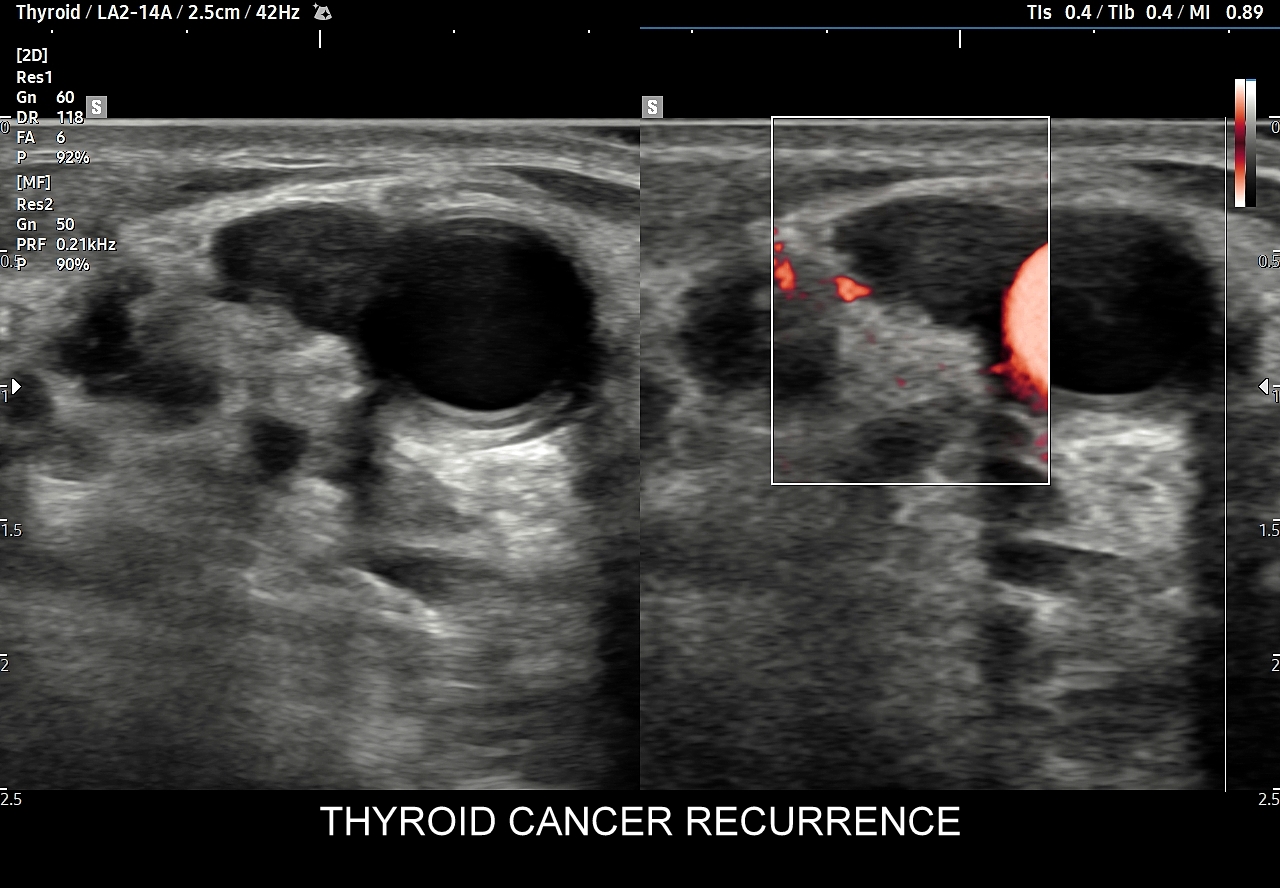

10. Guzy tarczycy. Klasyfikacja TIRADS.

Multiparametryczne badanie USG (MPUS) jest rozwinięciem klasycznego USG tarczycy i szyi pod postacią jednoczasowego zastosowania różnorodnych technologicznie trybów obrazowania USG, zarówno tzw. „nowych”, jak i „starych”. Wśród nowych najważniejszym jest obrazowanie mikrounaczynienia (MVI / MVF), w dalszej kolejności tryb elastograficzny oraz B-flow. Wymienione „nowe” modalności w połączeniu ze „starymi”, przede wszystkim z Dopplerem spektralnym i color-Dopplerem, stanowią rdzeń nowoczesnej ultrasonografii MPUS, gdyż umożliwiają pozyskanie znacznie większej ilości informacji z badania USG szyi w porównywalnym przedziale czasowym, a przez to uzyskanie jego większej wartości diagnostycznej.

Przykładowo badanie MPUS umożliwia różnicowanie guzów, ocenę żywotności tkanek i biologii nowotworów, poprawia obrazowanie dużych naczyń krwionośnych oraz ocenę podejrzanych torbieli. Z kolei zastosowanie badania USG z kontrastem (CEUS), jako kolejnej modalności rozszerzającej MPUS, daje w wyselekcjonowanych przypadkach korzyści m. in. w postaci różnicowania i oceny zmian ogniskowych, czy oceny skuteczności terapii ablacyjnych.